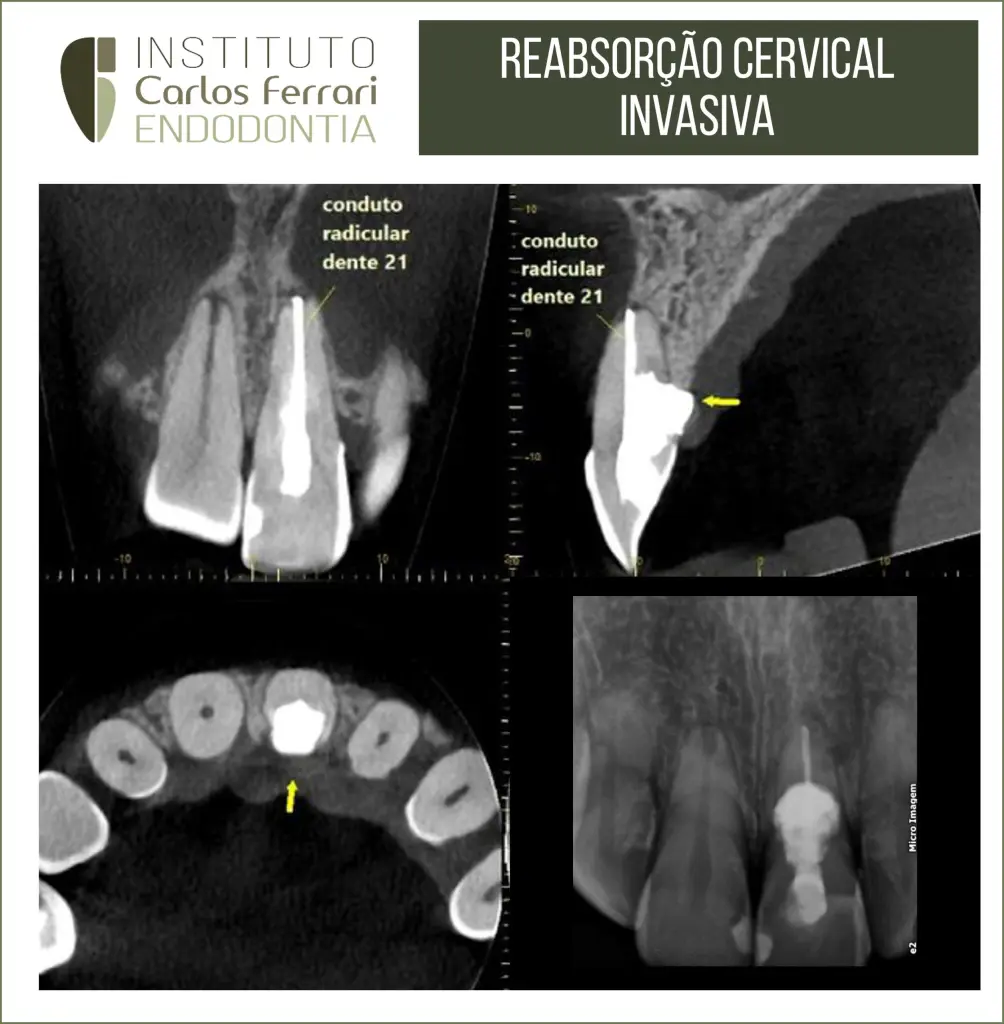

Reabsorção radicular cervical externa. Paciente 30 anos, sexo feminino, com diagnóstico de reabsorção radicular cervical invasiva, após queixa de dor na região gengival palatina. Na primeira sessão foi realizada a descontaminação do espaço endodôntico e medicação com Bio C Temp (Angelus).

Após 30 dias, com remissão total de sinais e sintomas, realizou-se a obturação do canal radicular com guta percha e cimento Bio C Sealer (Angelus) e preenchimento dos espaços com bio C Repair (Angelus).

Caso conduzido pela aluna Raissa Fleming, da atualização em endodontia da APCD Bragança Paulista.